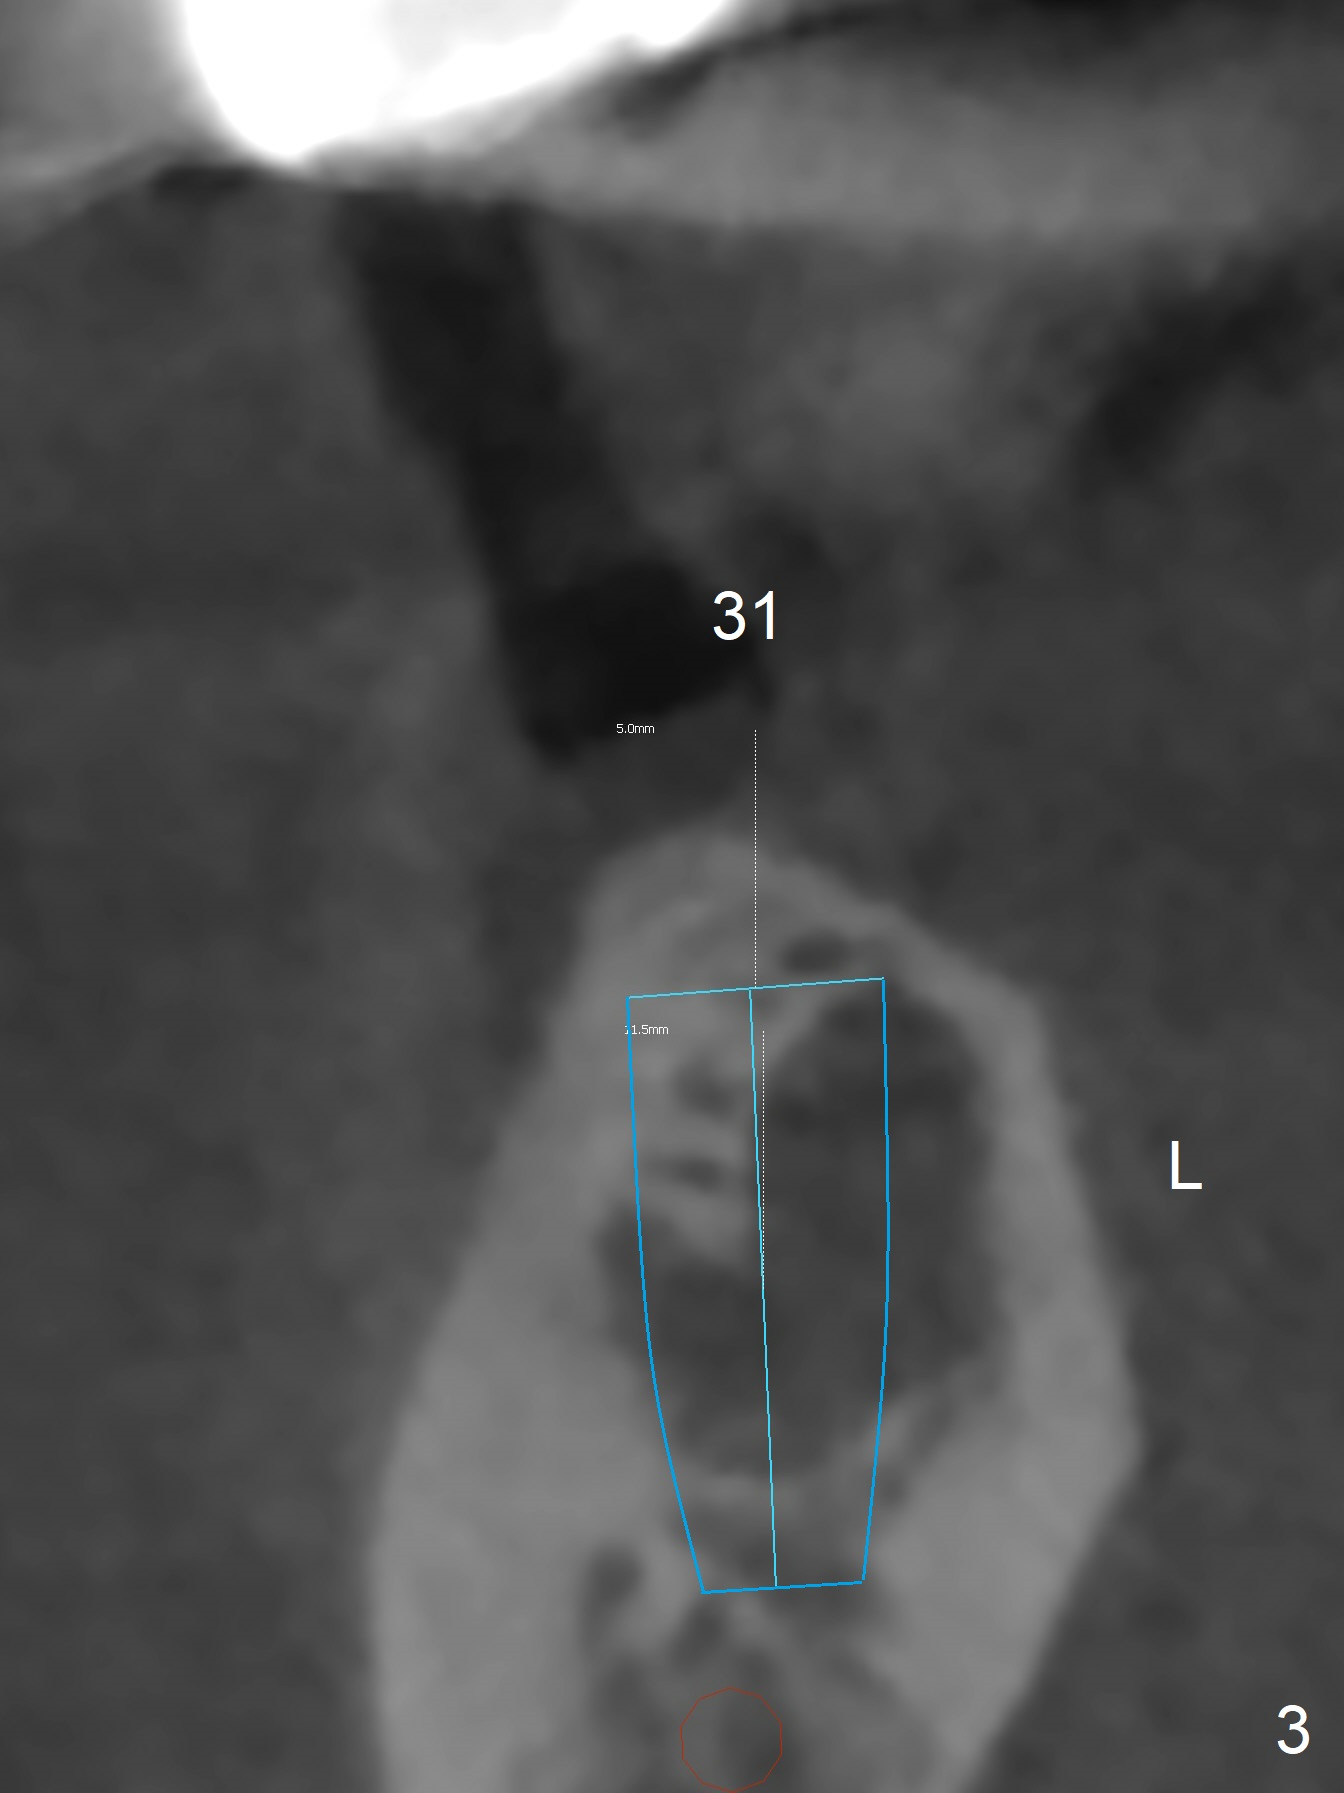

A 58-year-old man has lost the teeth #18 and 31 with supraeruption of the opposing teeth and mesial tilt of the distal tooth (Fig.1,2 arrows). Since the supraeruption is less severe on the right side (due to the presence of the tooth #32 as an antagonist to supraeruption of the tooth #2 (Fig.1' (arrow), as compared to Fig.2')), an implant will be placed at #31 with guide first (Fig.3 (coronal section of CT)). It is pity not to ask the lab to place the implant slightly distal for #32 upright. It is important to take impression for precise analysis of localized malocclusion. Intrusion of #2,15 will be initiated at the same time (Fig.4,5 (axial sections)), while the implant placement at #18 will be done last (Fig.6).